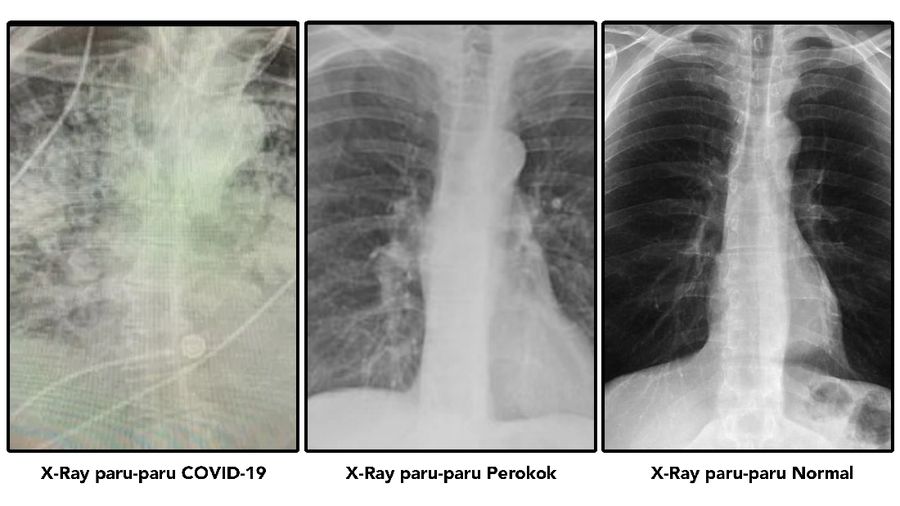

Jakarta, CNBC Indonesia - Baru-baru ini, heboh gambar X-ray mengejutkan para warganet. Bagaimana tidak, pencitraan X-ray itu menunjukkan bahwa jaringan parut dan kerusakan yang tertinggal pada pasien virus corona yang telah pulih.

Mengutip The Sun, Senin (18/1/2021) paru-paru orang yang sudah pulih dari Covid-19 itu bahkan lebih buruk daripada di paru-paru bagi para perokok.

Pada satu gambar rontgen menunjukkan sepasang paru-paru yang normal dan sehat, Pada foto lainnya yakni rontgen milik perokok, tampak sepasang paru-paru yang sebagiannya tertutupi warna putih.

Sedangkan paru-paru pasien Covid-19 yang tampak pada foto rontgen terlihat didominasi oleh warna putih dan hampir tidak jelas terlihat.

"Saya tidak tahu siapa yang perlu mendengarkan ini, tetapi paru-paru pasca-Covid-19 tampak lebih jelek daripada segala macam paru-paru buruk milik perokok yang pernah kami lihat," ungkap Dr Bankhead Kendall.